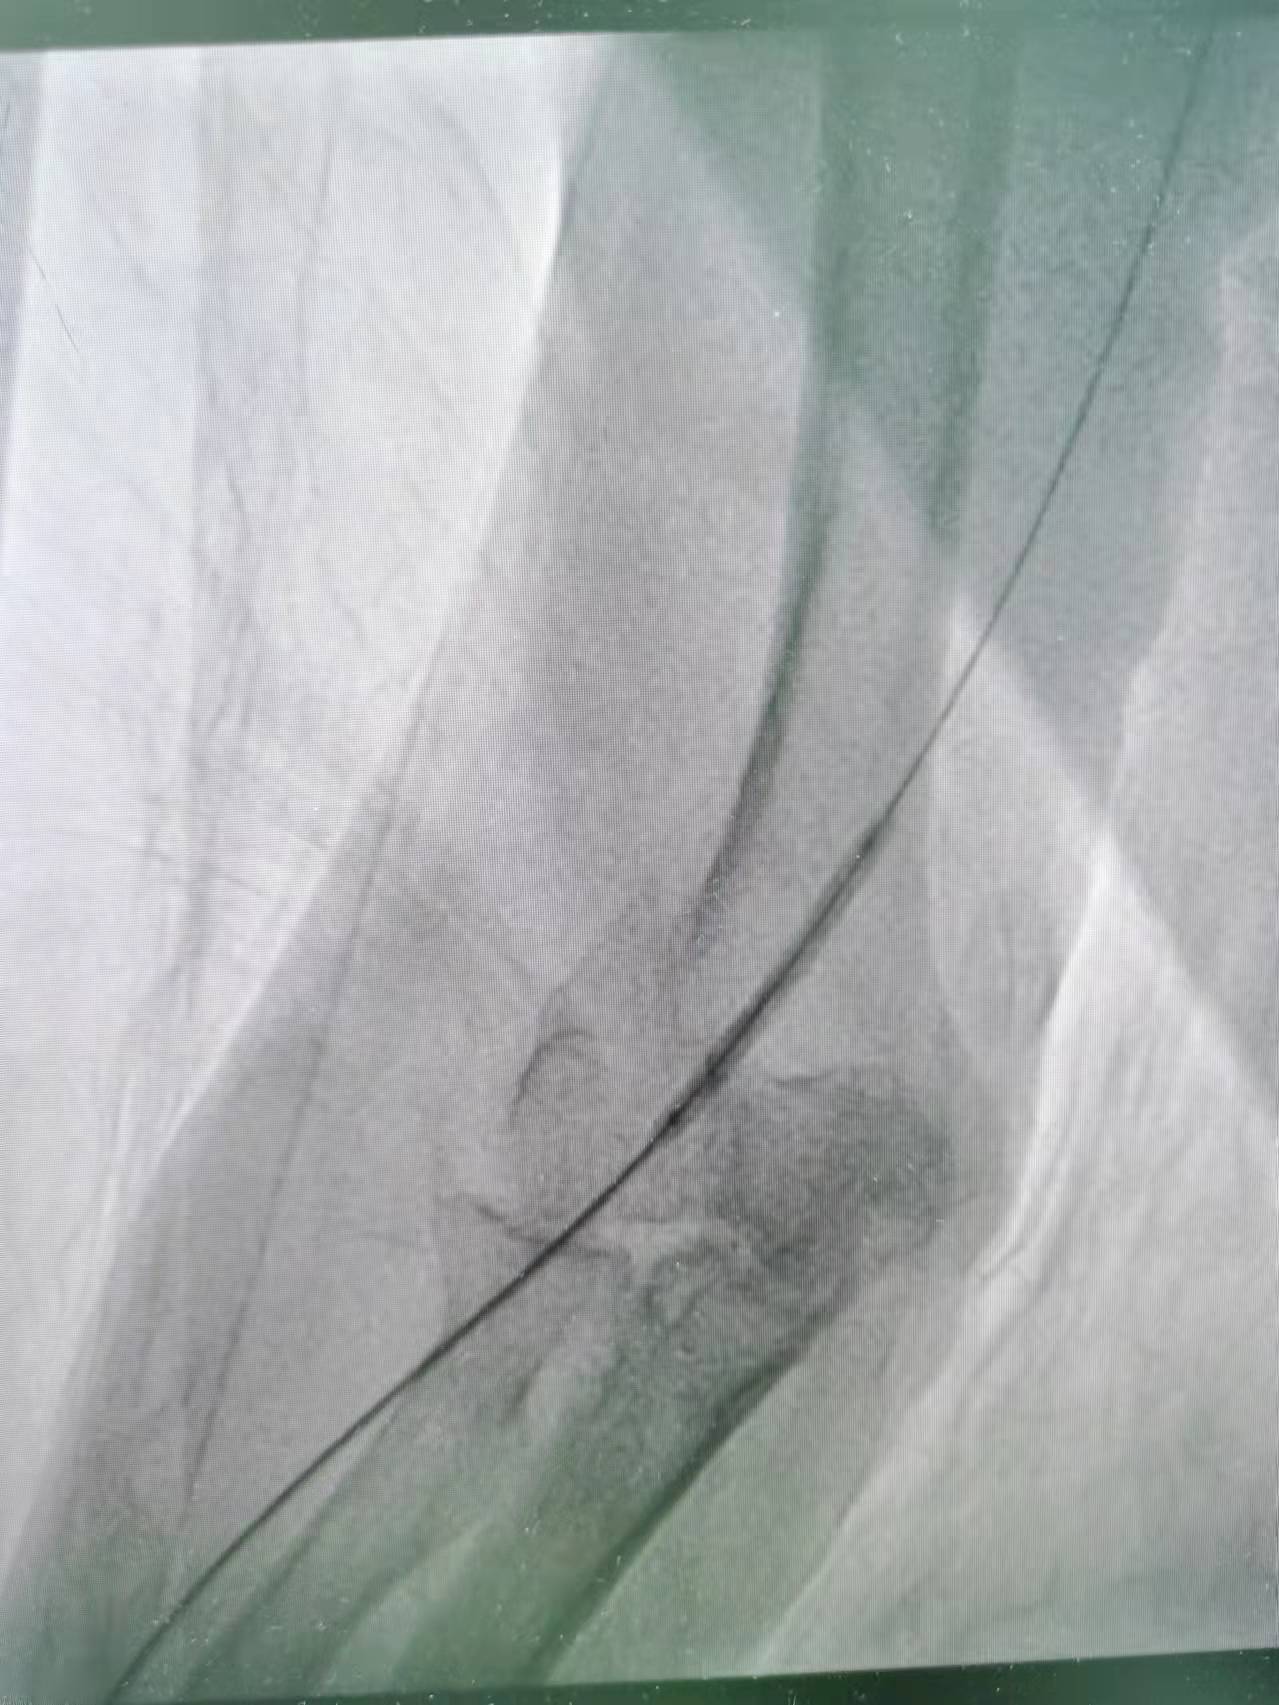

术中,李友河主任及肾内科团队予以在手术部位常规消毒、铺巾、局麻后选择远端桡动脉为穿刺入口,在彩色B超指引下穿刺成功后,按导入血管鞘,血管鞘导入泥鳅导丝,在彩色B超和x线曝光下导丝过内瘘口至头静脉直至贵要静脉近心端再 至上腔静脉,但未入右心房,于以肝素2000U血管注入,影显示内瘘口近心端3cm处头静脉段 重度狭窄, 长约1.2cm;手术过程顺利,术后宗叔血液透析流量良好,可达250ml/min,顺利完成血液透析。目前宗叔已康复出院且内瘘功能良好。

近心端狭窄扩张

近内瘘口狭窄扩张